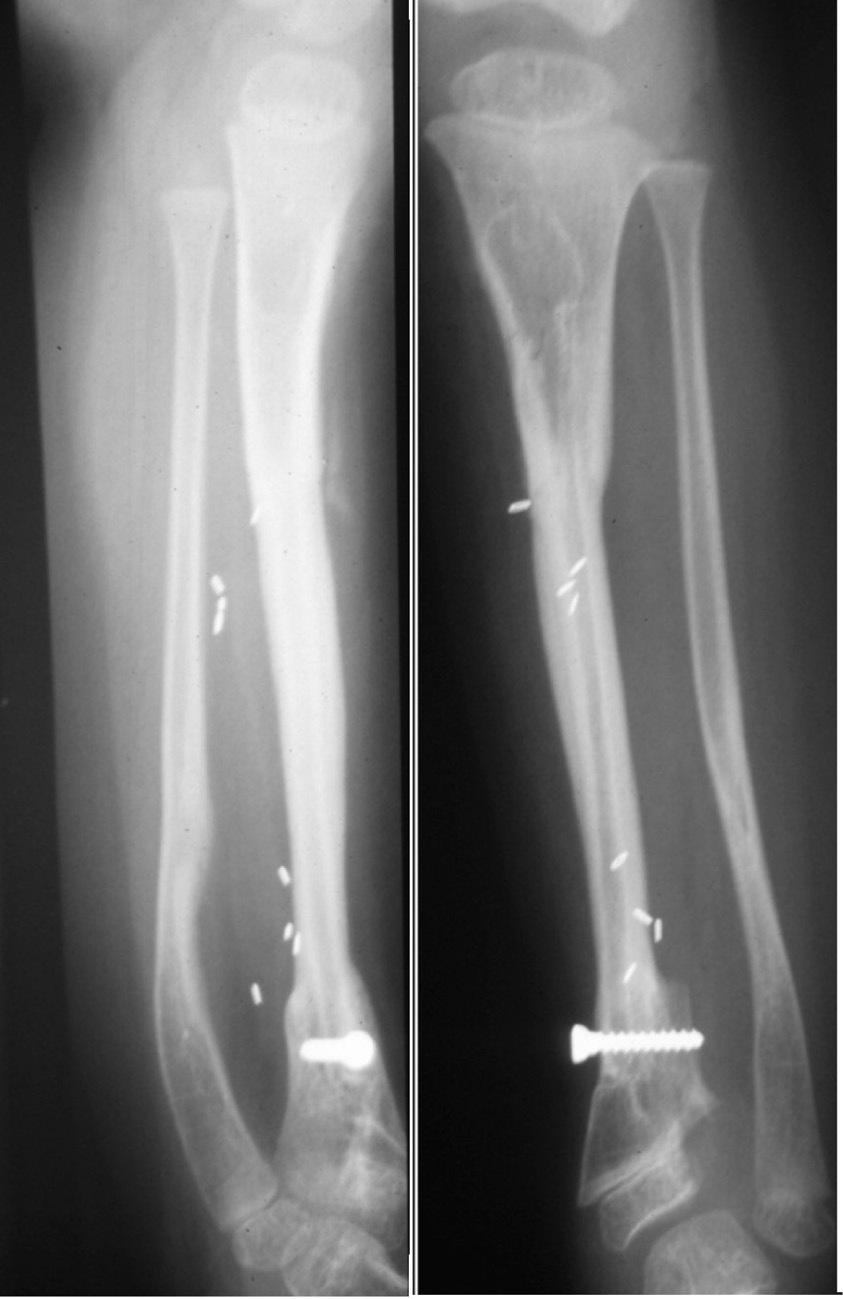

The same applies in the tibia, where the fibula is placed always within the medullary cavity of the bone. There it has been maintained again with the external fixateur or simply an above-knee plaster cast. Notably hypertrophy is frequently initiated by an undisplaced, often unidentified stress fracture as shown in Cases 1, 9, 10 and 11 (Figures 5, 30 and 31). If a specific fixateur is unavailable, in an emergency several transverse pins, a bit of bone cement and any nearby long metal rod or stick will do!

Another form of fixation is an intramedullary nail or rod used in two of our nine cases of resection of a pseudarthrosis of the tibia in a child shown in Cases 12 and 13 (Figures 32 and 33). In these two cases, the distal tibial fragment could not be fixed to the fibula with a screw. Instead a Rush nail was passed from below through the heel, calcaneum, talus and distal tibia and into the medullary cavity of the transplanted fibula. The result was exactly the same as the other seven cases. Even in plaster you can’t keep a child still! By six weeks all, including the two with nails, showed union and early bone hypertrophy (Figures 32 and 33).

The importance of centralising the fibula within the medullary cavity of the femur or tibia is again reinforced by another case done at the Royal Melbourne Hospital. The fibula was used to reconstruct the femur but fixed rigidly with a plate and screws in Case 14 (Figure 34A). Twelve months later there was union but no sign of hypertrophy of the transplant. Then the plate broke. A Kuntscher nail was inserted from above and down through the medullary cavity of the fibula. It shattered forming a row of ‘bangles’ around the nail (Figure 34B). Two years later, having walked on his ‘box of bones skewered by the K-nail,’ he was located and the leg radiographed. Except for one level, there was union and hypertrophy of all bone bangles (Figure 34C).